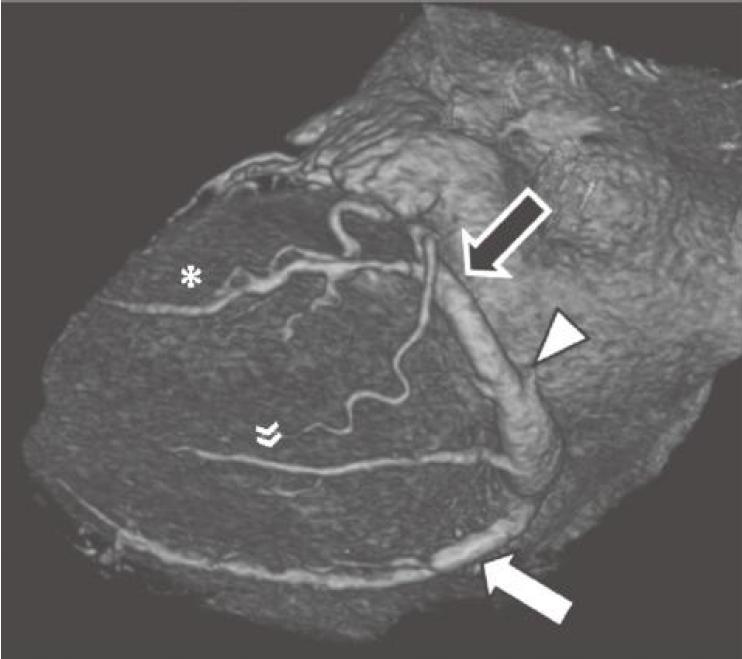

通常,RCA自右冠窦前方发出后在右房室间沟(RAVG)内向前然后向下走行,到达心脏的后方(图13-3及图13-4)。

图13-3 RCA(白箭)起自主动脉的前部,并沿RAVG(黑箭)走行。图中还可见位于前室间沟内(箭头)的LAD

AO.主动脉;PA.肺动脉;RA.右心房;RV.右心室;LV.左心室

图13-4 RCA优势型,RCA绕过右心缘,在RAVG的下方发出后降支(箭),并走行于后室间沟(虚线)。心中静脉(箭头)也在后室间沟内走行

RCA.右冠状动脉;RV.右心室;LV.左心室